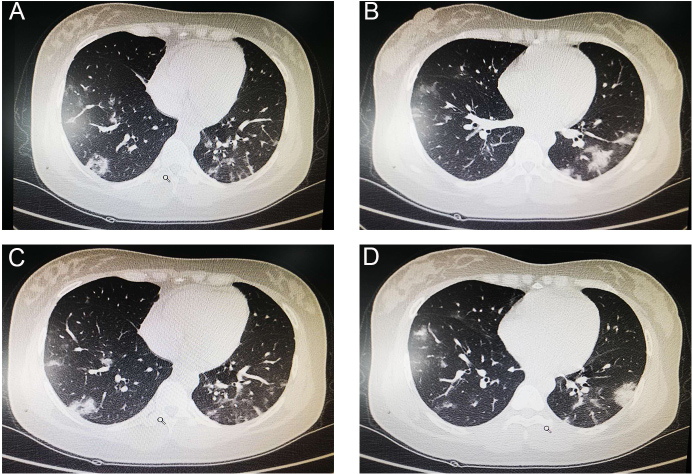

On February 6, 2020, a 30-year-old G5P1 female was admitted at 36 weeks and 3 days of her twin gestation to Wuhan Union Hospital, the designated institution for medical treatment of COVID-19 in Wuhan, China, for patients with confirmed diagnosis of COVID-19. The patient had a history of cesarean delivery seven years ago and no known hereditary disease. She self-reported having unprotected contact with a family member with confirmed COVID-19 diagnosis. She presented with an 8-day history of fever, cough, and generalized myalgia. Physical examination on admission revealed a temperature of 37.5 ℃, respiratory rate (RR) 22 breaths per min, blood pressure (BP) 112/70 mmHg, and heart rate (HR) 96 beats per min. There were decreased breath sounds and rales on lung auscultation. Pertinent laboratory results included hemoglobin 114 g/L, lymphocyte 1.03 G/L, lymphocyte ratio 19.4%, and C-reactive protein 34.12 mg/L. Other biochemical and coagulation parameters were within normal limits. The patient's throat swabs and fecal samples both tested positive for 2019-nCov by real-time reverse-transcription-polymerase-chain-reaction (rRT-PCR) assay, while a test of viral respiratory pathogens was negative for influenza A and B, parainfluenza, respiratory syncytial virus, mycoplasma pneumoniae, adenovirus, and coxsackievirus. Chest CT showed patchy ground glass opacities, consolidative lesions, and several fibrous stripes, mainly distributed in the subpleural regions of bilateral lungs, which is the typical manifestation of COVID-19, as shown in Figure 1. She was formally diagnosed with COVID-19 with her positive rRT-PCR result and chest CT findings. Given her diagnosis and presentation, the decision was made to perform an emergent cesarean delivery.

Figure 1: Chest CT findings of the patient. A-D, CT images showed multi-focal ground glass like shadows, consolidative lesions, and several fibrous stripes, predominantly involving the subpleural regions of both lungs.